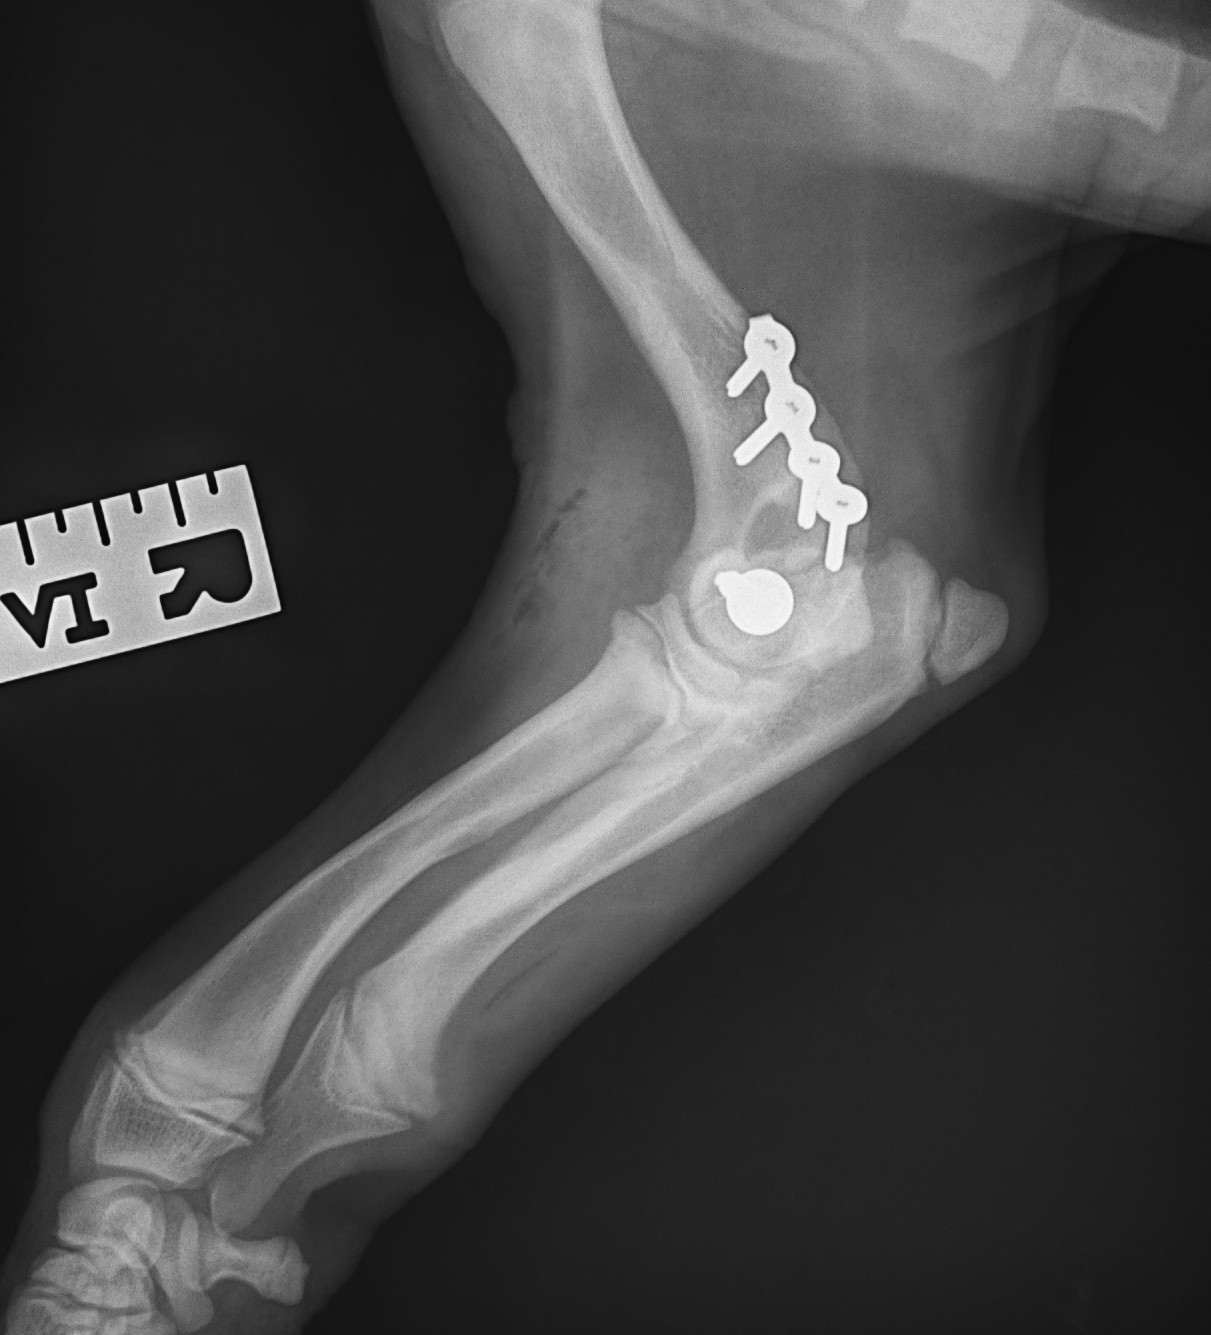

Otto came to us from another practice as we now offer surgical referrals to pets whose own practice can’t fix them for whatever reason. Simon put his elbow back together and put a screw across the elbow to hold it in position, with a small stainless-steel plate and screws across the broken ridge as well.

Otto’s owner now has the hard part – keeping Otto in a cage for 4 weeks :-0

He’s been a very good boy so far, so fingers crossed. It’s important that he rests strictly so that the bones can heal – if they heal in the position that they were when he came off the operating table, he will make a full recovery.